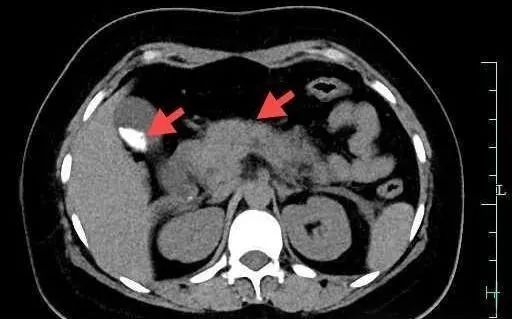

根据各项检查结果,结合小慧患有胆囊结石的既往病史,医生诊断她正是因为大量进食后而引起了急性胰腺炎,需要马上住院。在进行了一系列抗感染、止痛、抑酶等治疗后,医生给她做了胆囊切除手术。

医生表示,胰腺炎分为急性和慢性两种。急性胰腺炎常见的症状包括腹痛;恶心、呕吐及腹胀;发热等,重症急性胰腺炎还会出现皮肤发黄、血压下降、脉搏变浅、呼吸困难、上下腹部皮肤出现大片紫色瘀斑等。有几类人群比较容易“中招”,因此在日常生活中控制食物摄入的量还是非常有必要的。

在中国,三类人群比较容易得胰腺炎。一个是有胆道疾病的人群,比如说有胆囊结石、胆管结石;第二个是比较肥胖的病人,有脂肪肝、 高脂血症的病人;第三个就是长期酗酒的人群,这些人群比较容易得急性胰腺炎。

急性胰腺炎的疼痛和普通的胃疼比,急性胰腺炎是比较剧烈的,急性胰腺炎一般是左上腹痛。如果大家发现自己有发热、皮下有瘀斑、疼痛非常剧烈的时候,建议还是尽快到医院,医生来进行诊断。